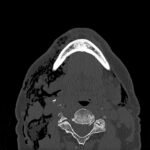

Subcutaneous emphysema (SE) is a rare but significant complication following dental procedures characterized by the presence of air in the subcutaneous tissue. This case report presents a 67-year-old male who developed right-sided facial swelling after tooth extraction, a procedure executed with high-power dental tools. Clinical findings included facial swelling and crepitus with no lip involvement, differentiating SE from an allergic reaction and hematoma. Diagnostic imaging through computed tomography (CT) and chest X-ray confirmed SE, showing diffuse subcutaneous air in facial and neck soft tissues. Initial management in the emergency department (ED) involved administration of antihistamines, corticosteroids, antibiotics, and otolaryngology (ENT) consultation with close monitoring for airway compromise. This case underscores the importance of including SE in differential diagnoses for post-dental procedure swelling, the effectiveness of CT imaging in SE identification, and the importance of early detection and treatment to prevent severe complications like respiratory and cardiac issues.